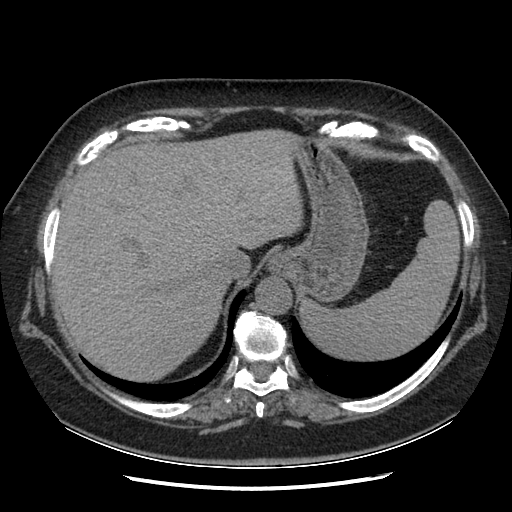

Original VENOUS CT scan

Full window (WL 1023.5, WW 4095 → Low −1024, High +3071)

Actual HU range: [-160.0, 240.0]